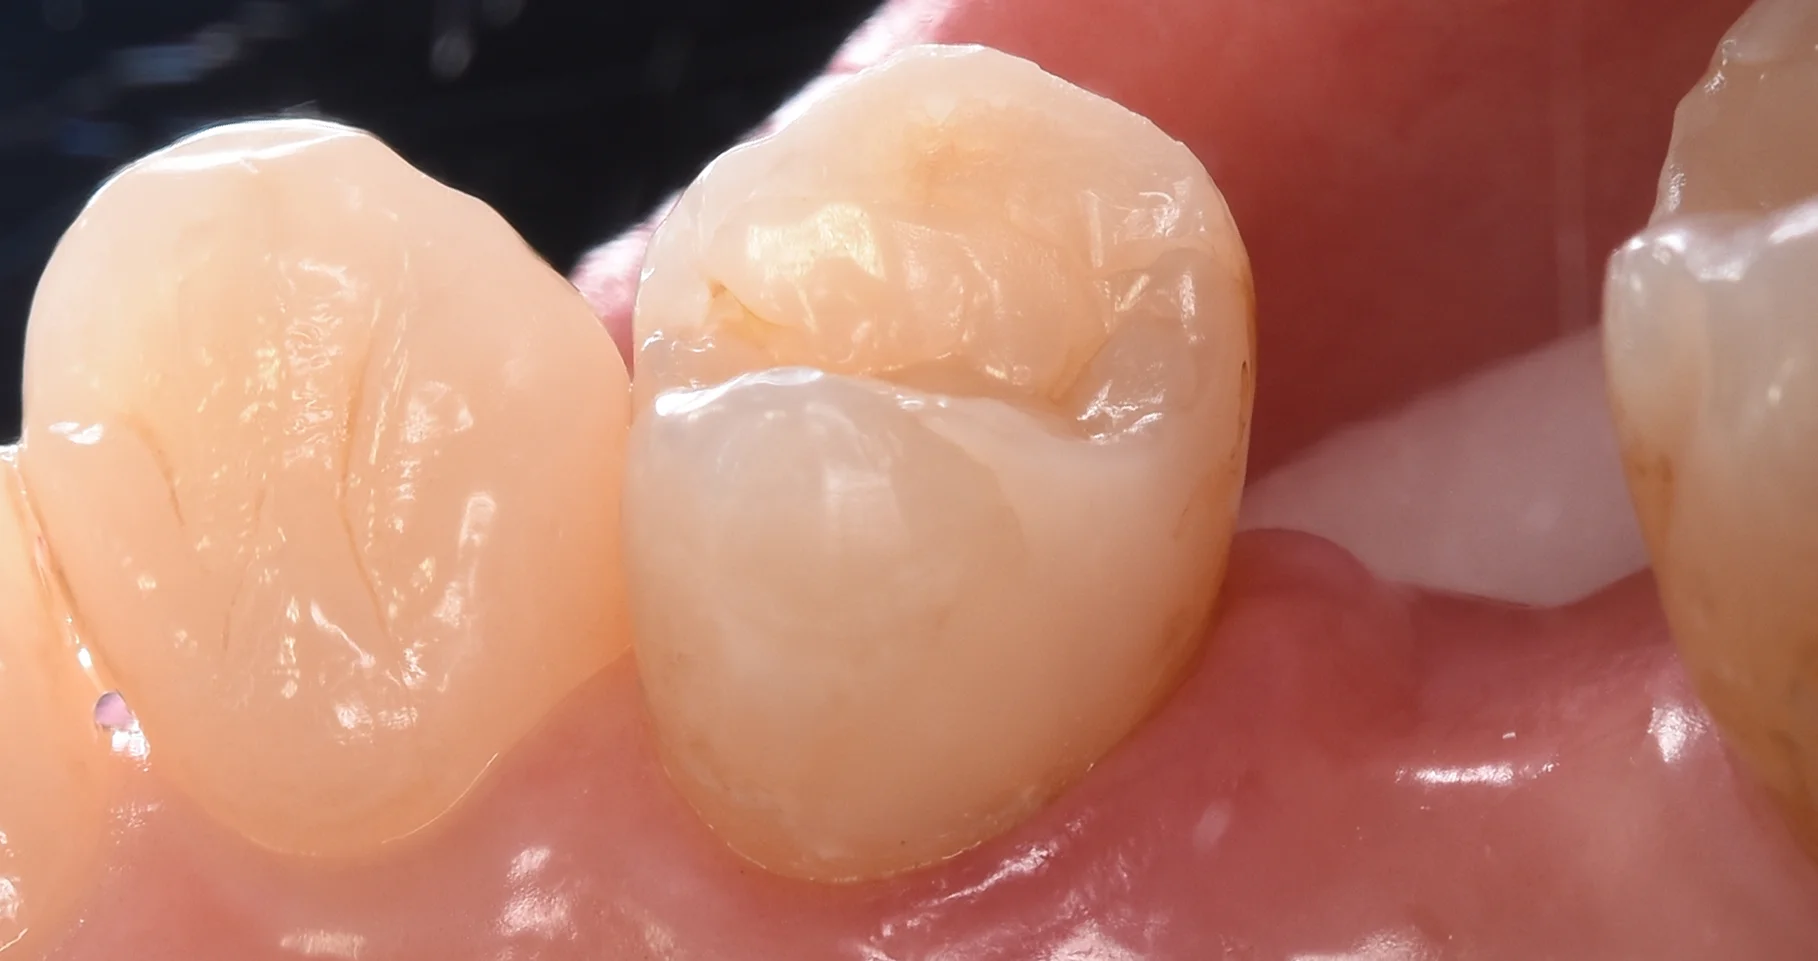

そして、虫歯の部分のみを除去し切ったのがこちらになります。

今回は歯が削れていない部分も含め、歯が脆くなっているところも除去しました。

昔と今では少し考え方が変わってますので、こういう変化になりますね。

多分この初回の治療を行った当時であればまたこの穴が開いていた部分だけを治療していたと思います。

そして詰め終わったのがこちらです。

段差もなく綺麗に詰め終わることができましたヽ(゚∀゚)ノ パッ☆

4年越しの治療になりましたが、前の治療も状態としては良好ですので、今後も長く使っていけると思います!